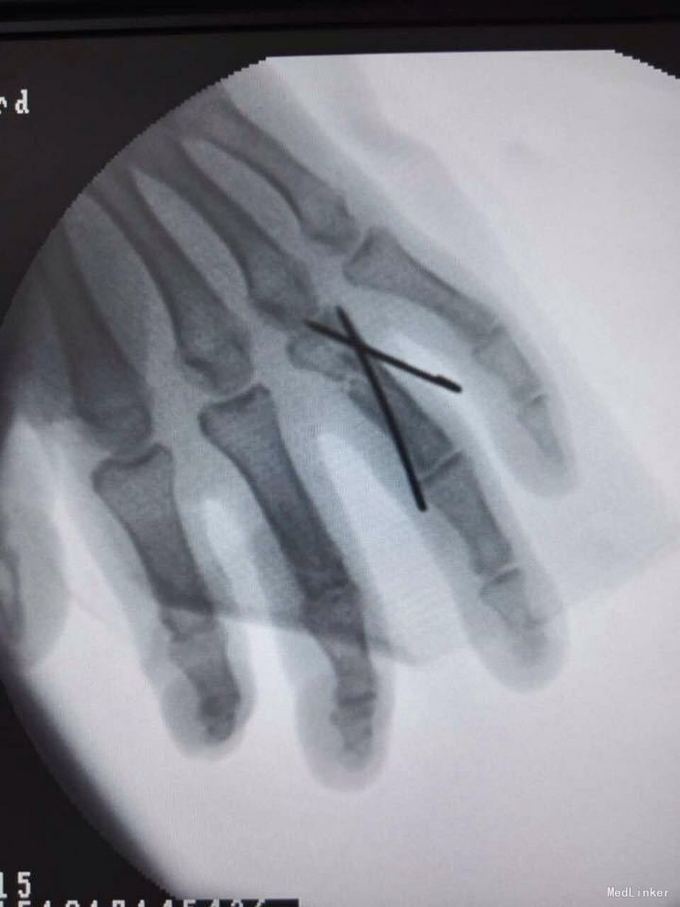

环指开放性骨折 伸指肌腱断裂 予以清创缝合 指骨骨折克斯针内固定 肌腱修复

术后予以石膏托外固定 手指被动屈伸训练